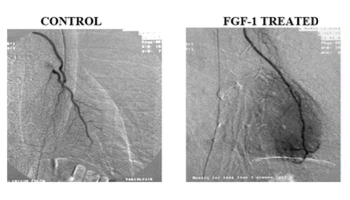

Comparison of two medical images showing blood vessels, labeled 'Control' on the left and 'FGF-1 Treated' on the right, illustrating blood vessel growth and repair.

In a US FDA Phase I Clinical Trial, FGF-1 was able to grow around blocked arteries in the heart. By growing around these blocked arteries, FGF-1 was able to treat coronary artery disease, allowing for these patients to reduce chest pain and begin to return to normal. The plush shown on the right side indicates new blood vessels growing around blocked arteries in the heart.

In all 20 patients that received FGF-1, a blush of new blood vessels could be observed on angiograms. Blood vessel density increased by three times and remained three years after the treatment, supplying blood and nutrients to the heart.